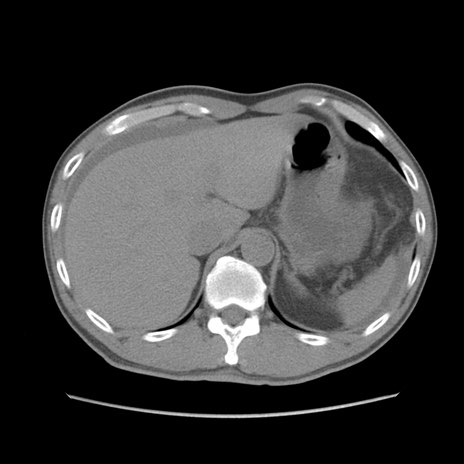

症例56 CT(横断像)

脂肪ウインドウ